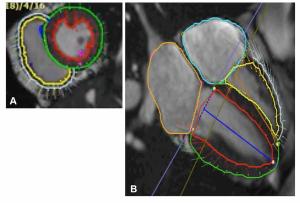

Incorporating AI to reduce artifacts and bolster soft tissue contrast, the Elekta Evo CT-Linac system reportedly improves detection of tumors and organs-at-risk.